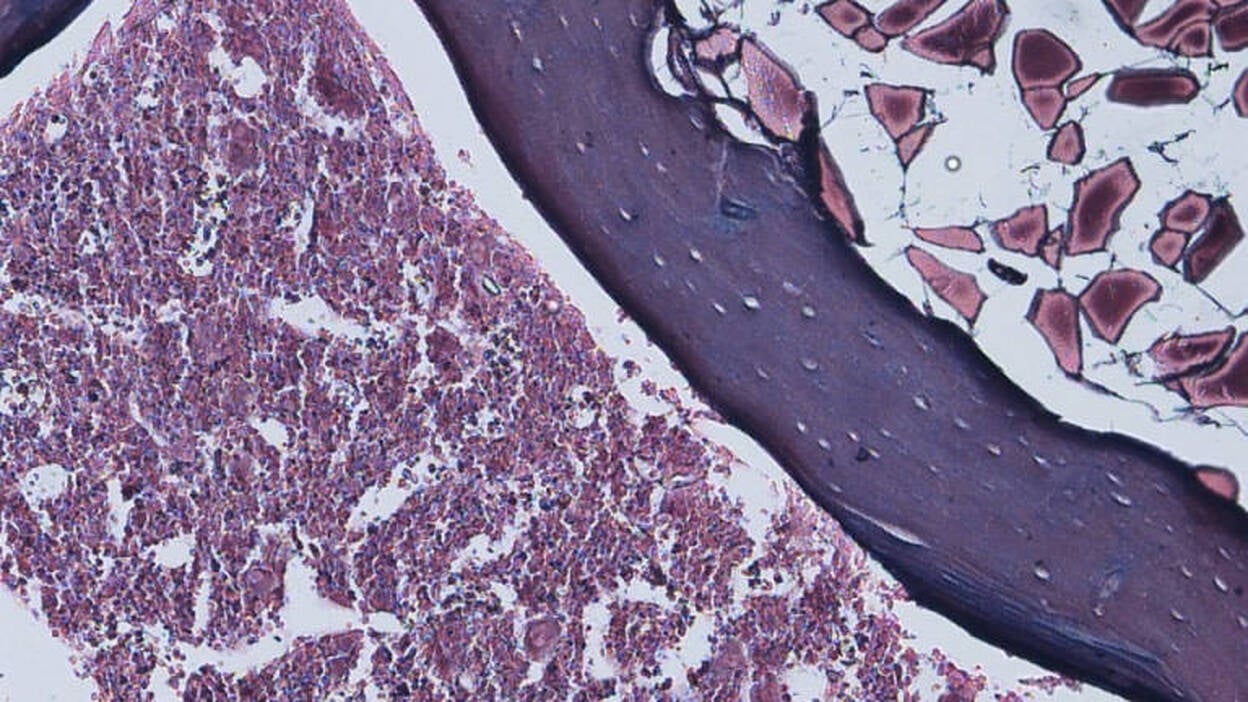

Un estudio del Laboratorio de Regeneración Tisular y Neuronal del Centro de Investigación Príncipe Felipe (CIPF), dependiente de la Conselleria de Sanidad Universal de la Comunidad de Valencia, revela que el uso de fármacos para manipular una proteína de las células potenciaría la regeneración neuronal tras una lesión medular. Según la investigación, la modulación farmacológica de un canal iónico (proteínas que determinan importantes procesos en los seres vivos) "podría controlar tanto la replicación de las células madre como su diferenciación a células maduras con aplicación en la reconstrucción de tejido neuronal en terapias regenerativas". El estudio, llevado a cabo por la doctora Victoria Moreno, revela por primera vez que el canal iónico Conexina 50 está presente en "grandes cantidades" en las células madre de la médula espinal y que los niveles de esta proteína se reducen "significativamente" tras una lesión medular, según ha informado la Generalitat en un comunicado. Los resultados de la investigación han sido publicados en sendos artículos científicos de 'International Journal of Molecular Science' y 'Cell & Tissue Research'. Según la doctora Moreno, se ha explorado el papel de esta proteína de las células ependimarias (de la médula espinal) en la modulación del control de la renovación de las células madre de la médula espinal. Todo ello en conjunto con otro conocido regulador, la proteína Sox2, "esencial en el mantenimiento del estado indiferenciado de las células madre embrionarias, y que ha resultado ser un factor clave en la reparación de tejido neuronal." Las investigaciones del grupo de Regeneración Neuronal y Tisular han mostrado que existe un papel dual de esta proteína dependiendo de su localización. Así, cuando la Conexina 50 se encuentra en el núcleo junto a la proteína Sox2, ésta mantiene la capacidad proliferativa de las células madre, y cuando la Conexina 50 se encuentra en la membrana celular, favorece la diferenciación a células que intervienen activamente en el procesamiento cerebral de la información en el organismo. ESTUDIOS IN VIVO E IN VITRO Los diversos experimentos realizados 'in vivo' e 'in vitro' con clotrimazol (agente antimicótico con capacidad de inducir la expresión de Conexina 50) han puesto de manifiesto, además, una mayor expresión de Sox2 en el tejido de la médula espinal tras una lesión bajo el efecto de este fármaco. A pesar de que las investigaciones demuestran que existe una necesidad de mantener un control de la localización de este canal iónico para interferir con la diferenciación de estas células madre, el estudio concluye que la modificación farmacológica de la Conexina 50 induce a potenciar la regeneración de tejido neuronal endógeno. Este descubrimiento tiene una importante aplicación en tratamientos de regeneración celular.